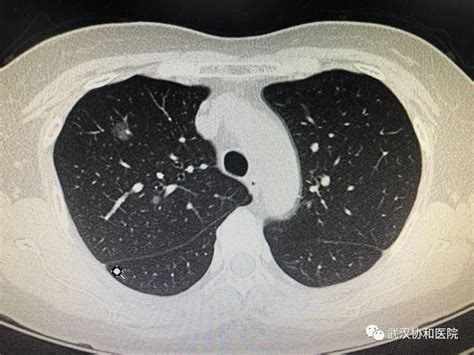

肺结节及其他

1、病理描述相当明确,倾向结核。结核诊断的金标准是找到结核杆菌,而病理只是结核杆菌感染后病变的样子而已。所以,这个病理已经相当典型了。2、手术方式:局部切除或者肺叶切除?3、胸外科一般认为此类患者需抗结核治疗,但目前结核治疗必须到指定医院。建议至肺科医院就诊。一般还需再查痰找抗酸杆菌等。

上海市中山医院-胸外科-王群主任医师